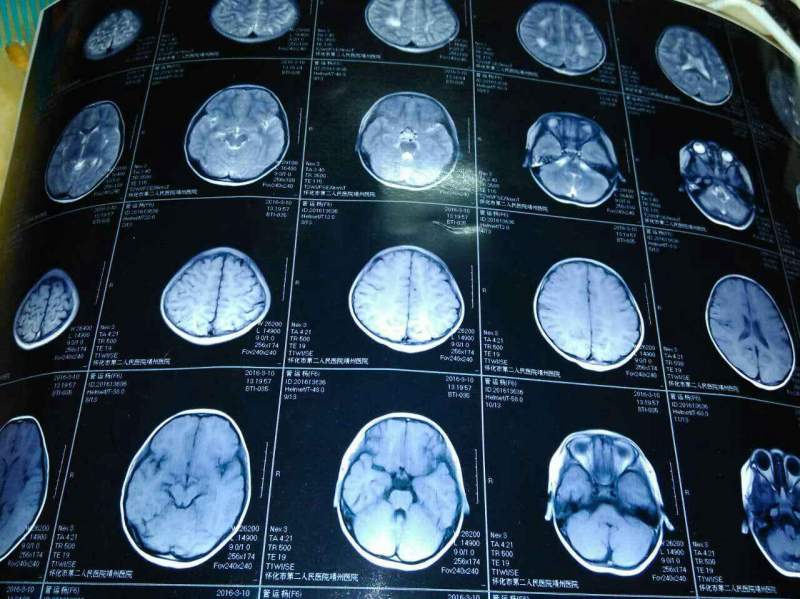

小妹今年六岁,身体看着挺健康的,没什么病痛,只是三岁左右查出有远视眼,视力不好。但前几天查脑部核磁,医生说可能有问题。万分交集,在此求助万能的虫友,万分感谢! 发自小木虫Android客户端 |